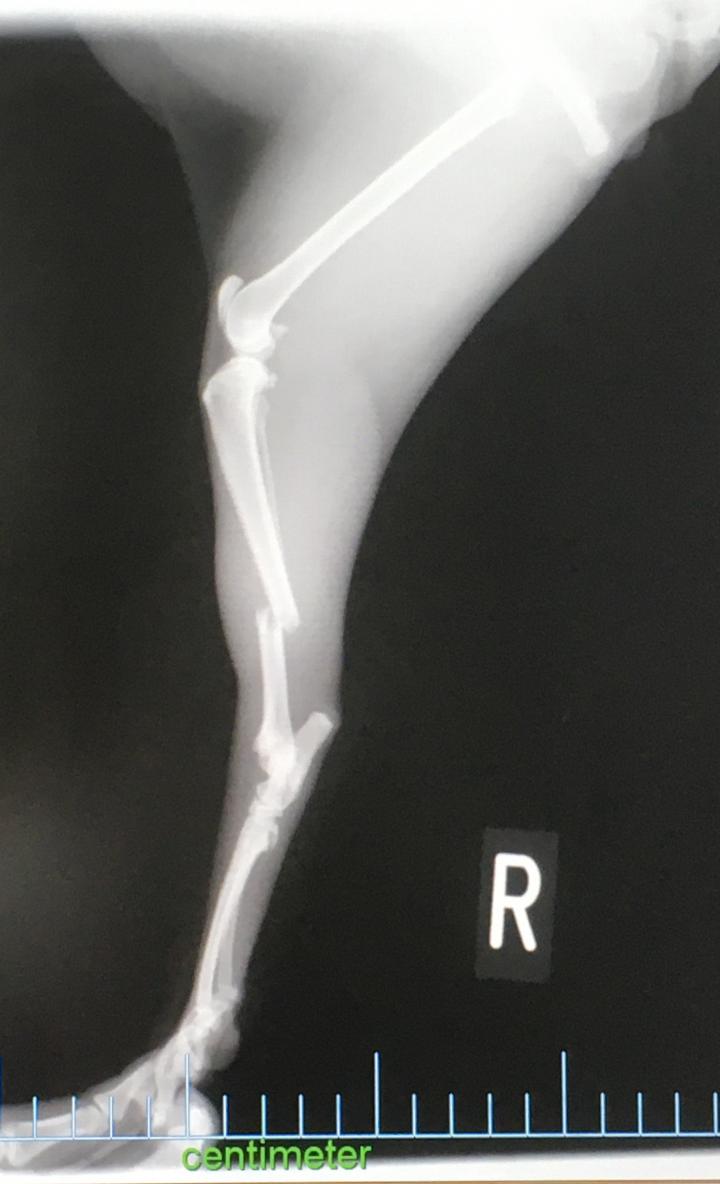

7月24日夜(7時くらい?) 骨折

7月25日 朝骨折発覚、地元病院 → 札幌の病院

7月26日 午後手術

プレート2本、ボルト8本入れる